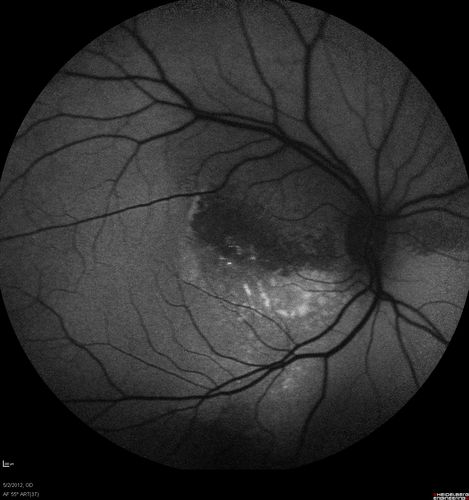

autofluorescence. od

autofluorescence helps localize the subretiinal fluid

Coats disease